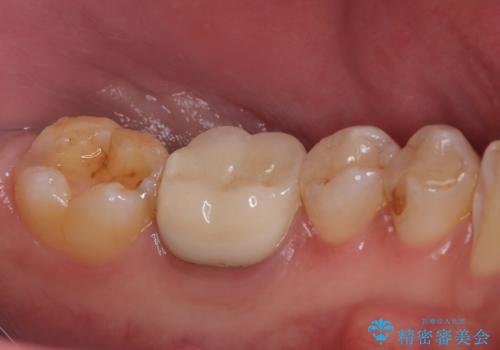

銀歯がとれた セラミックインレーで修復

- 銀歯が取れたとのことで来院されました。

拡大鏡下で丁寧に虫歯を取り除き、セラミックインレーによる修復治療を行いました。

今回は銀歯が取れたので、虫歯が神経まで達して痛みが出る前に、強度・審美に優れ、虫歯の再発の少ないセラミックインレーにて治療を行うことができました。